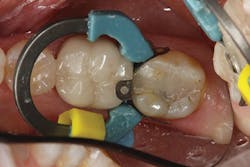

However, as mentioned earlier, getting the composite adapted to both the buccal and lingual cavosurfaces at the same time can be tricky. To address this, I have found it easier to place one increment of resin in a way that covers the entire buccal side of the preparation, including the marginal ridge area (figure 2), and light cure it prior to finishing the fill with the lingual increment. This requires one extra step, but it gives me the peace of mind that I am reducing the polymerization shrinkage on the opposing cavosurfaces as well as eliminating the back and forth nature of trying to adapt the composite to both sides of the cavity preparation (figure 3).